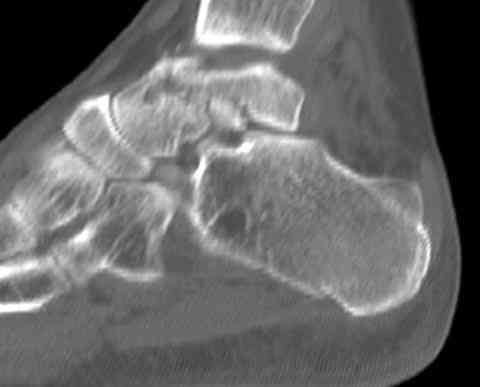

Случай с множественным оскольчатым переломом тарана оперированный из двойного доступа.

Через 2 мес.: